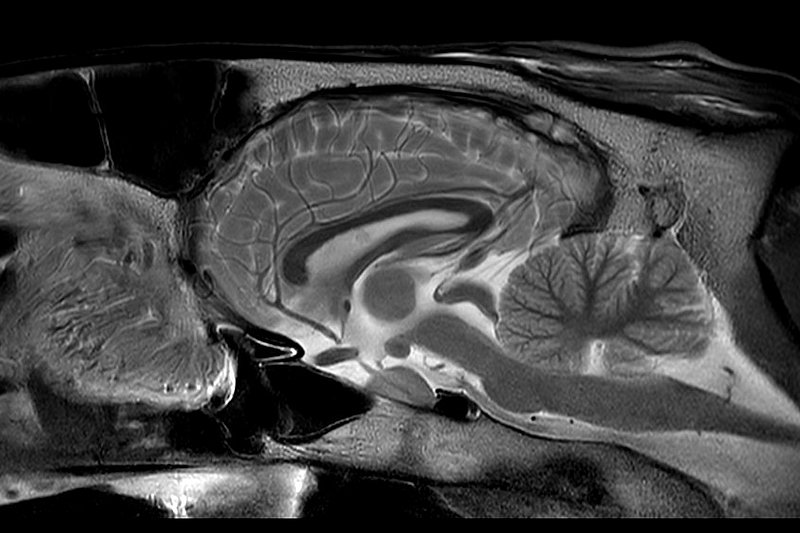

Magnetresonanztomographie - MRT

- Bei der Magnetresonanztomographie werden Schnittbilder von Organen und Gewebe durch Magnetfelder und Radiowellen gemacht. Das MRT-Gerät besteht aus einer Röhre. In dieser Röhre werden durch das Magnetfeld und die Radiowellen die Wasserstoffatome im Körper des Pferdes ausgerichtet und die Signale gemessen.

- Die Klinik für Pferde nutzt das Hochfeld MRT (3Tesla) der Kleintierklinik für die Untersuchungen. Deshalb entstehen Bilder von sehr guter Bildqualität. Allerdings ist dafür eine Narkose des Pferdes notwendig.

- Es können sowohl die Zehen, als auch Vorderfußwurzelgelenk, Sprunggelenk und das Gehirn untersucht werden.